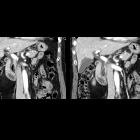

MRCP

Focal outpouching of the duodenum adjacent to the papilla (usually 2 part of the duodenum) causing compression of the CBD.